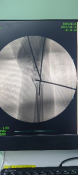

術中透視

患者男性,54歲,外傷致右側脛腓骨開放性骨折8小時,局部可見右側脛骨骨折近端露出···